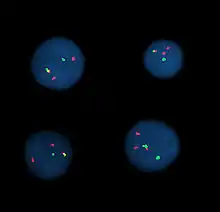

Fluorescence in situ hybridization

Fluorescence in situ hybridization (FISH) refers to using fluorescently labeled probe to hybridize to cytogenetic cell preparations.

Analysis

Analysis of FISH specimens is done by fluorescence microscopy by a clinical laboratory specialist in cytogenetics. For oncology, generally, a large number of interphase cells are scored in order to rule out low-level residual disease, generally between 200 and 1,000 cells are counted and scored. For congenital problems usually 20 metaphase cells are scored.